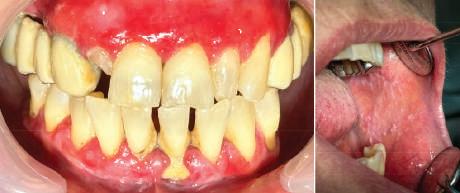

Examinarea parodontală a relevat sângerări generalizate la sondare și adâncimi de sondare de până la 9 mm la molarii maxilari și mandibulari, cu multiple furcații implicate la fiecare molar (fig. 2-7). Prezenta mobilitate multiplă de clasa I la dinții posteriori și de clasa II la dinții nr. 16 și 21 (molarul prim maxilar drept și incisivul central maxilar stâng).

2-4. Imagini înainte de tratament: lateral dreapta (fig. 2), frontal (fig. 3) și lateral stânga (fig. 4). Notă: Molarul prim maxilar drept (dintele 16) (fig. 2) ar fi identificat ca fiind molarul cel mai afectat parodontal care era planificat să fie menținut.

Figurile:

5, 6. Imagini ocluzale înainte de tratament: maxilar (fig. 5) și mandibulă (fig. 6).

7. Rx periapicale înainte de tratament.

8. Rx periapicală a molarului prim maxilar drept (identificat ca fiind molarul cel mai afectat parodontal care era planificat să fie menținut pe arcadă).